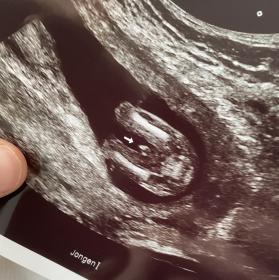

Tricky NUB 13+1 weeks? Long NUB but some stacking?

I had a scan yesterday (13+1 weeks!). During the scan I was convinced I saw long somewhat flat, but also a stacked nub (I saw a shadow in the background), but the tech said it was the stacking was the umbilical cord. The tech said she saw a flat NUB that I is why she was leaning more towards girl.

I posted my scans online and got mostly boy guesses (some girl because of the "flat" NUB) but I was wondering if it's still possible it might be a girl? That the "stacked thing" is something else??? (Already got 3 boys so a girl would be so welcome!)